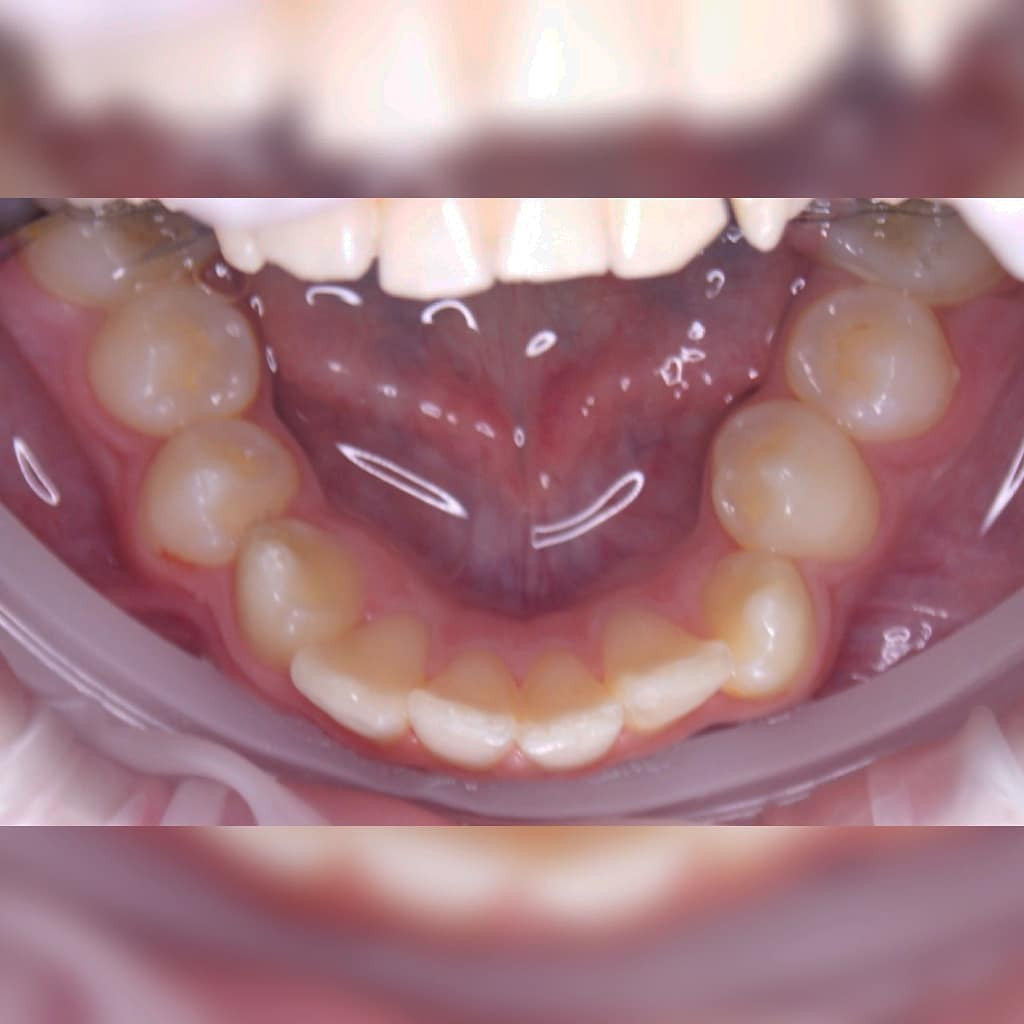

Эта фраза знакома многим ответственным родителям, которые привели на приём к ОРТОДОНТУ своего ребёнка в 5-10 лет, заподозрив проблему или понимая, что места постоянным зубам откровенно не хватает! Горькая правда в том, что брекеты - не волшебное средство от всех проблем, они "расставляют" зубы внутри сформированого объёма челюсти, но никак не влияют на её рост. Родители ждут, а тем временем драгоценное время, когда ребёнок растёт, уходит... Во взрослом возрасте приходится удалять здоровые зубы или прибегать к ортогнатической хирургической операции. 📸 На фото узкая нижняя челюсть, места постоянным зубам нет, боковые резцы прорезываются "вторым рядом".

✅ Помогаем с помощью расширяющей дуги, пружины и зацепных элементов, которые зафиксированы на МОЛОЧНЫЕ зубы